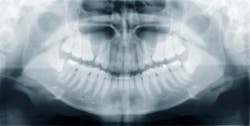

According to the National Institutes of Health (NIH), osteonecrosis is a disease where new bone does not replace old, resorbing bone quickly enough. The cause is attributed to less flow of blood to the affected area. (1) Osteonecrosis can occur in any bone, but we will discuss osteonecrosis of the jaw (ONJ).

According to the American College of Rheumatology, ONJ “is associated with cancer treatments (including radiation), infection, long-term steroid use, or potent antiresorptive therapies that help prevent the loss of bone mass.” (2) Some of these antiresorptive pharmaceuticals are bisphosphonates such as alendronate (Fosamax), risedronate (Actonel and Atelvia), ibandronate (Boniva), and denosumab (Prolia). (2)

The American Academy of Oral Medicine (AAOM) has a question and answer page on bisphosphonate therapy and its connection to ONJ. It mentions that ONJ has been reported by those taking bisphosphonates and having a procedure such as tooth extraction or other invasive dental procedures. The AAOM considers ONJ a rare side effect for those taking oral bisphosphonates. (3)